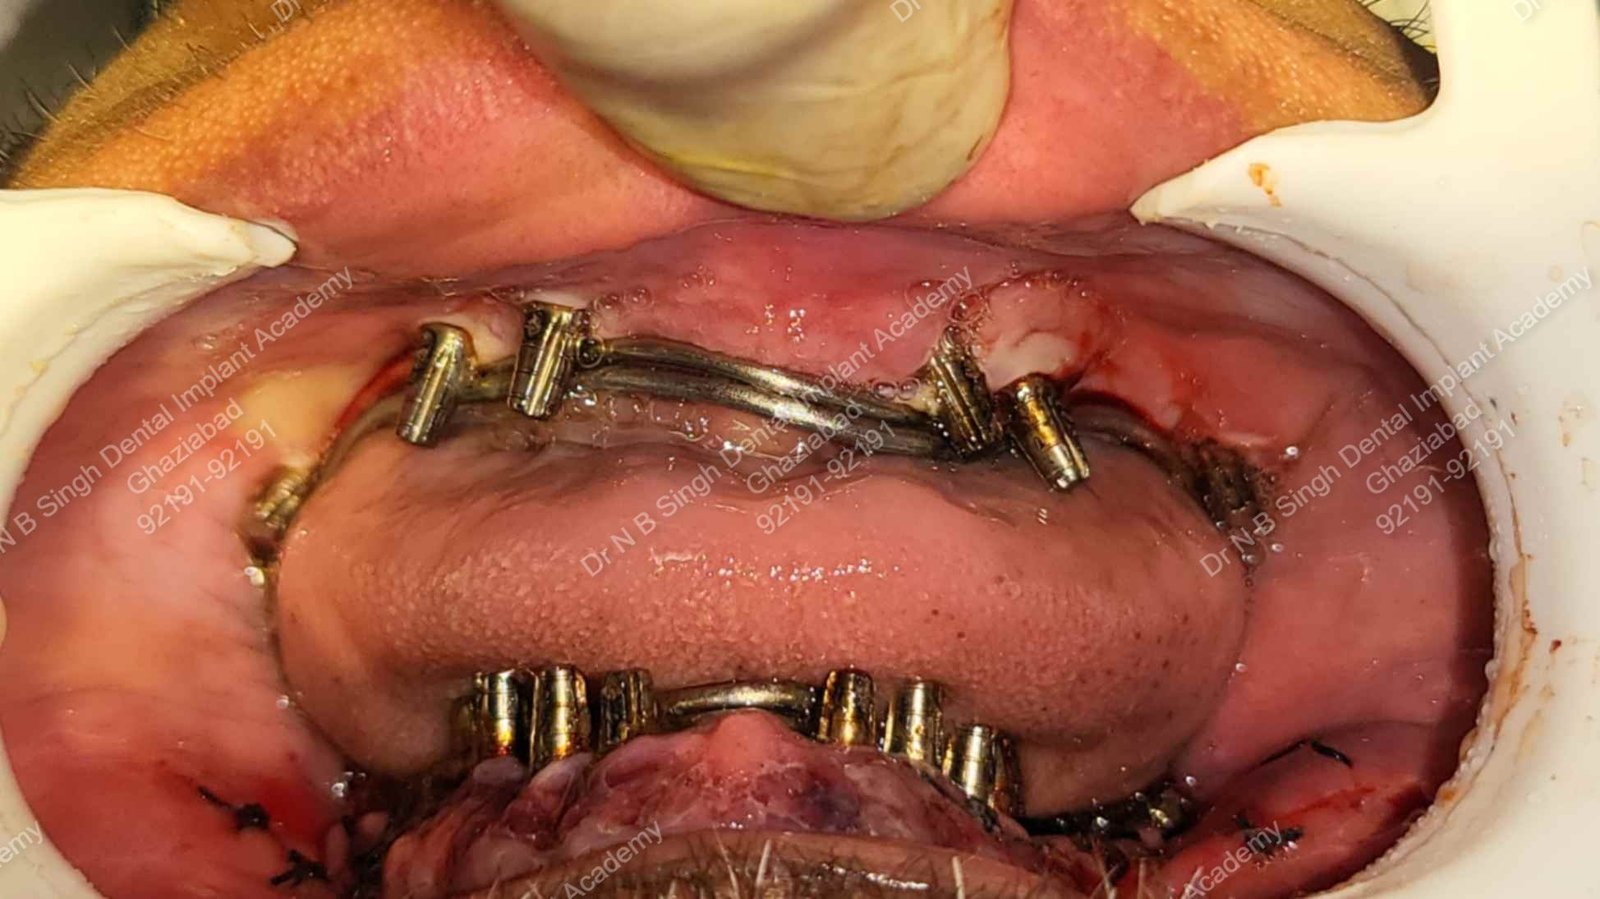

A007 bilateral smooth surface Redice zygomatic implants placed

A009 bbilateral smooth surface Redice zygomatic implants Bending

A009 Titanium 1.6 mm wire concretization [ intra oral welding ]